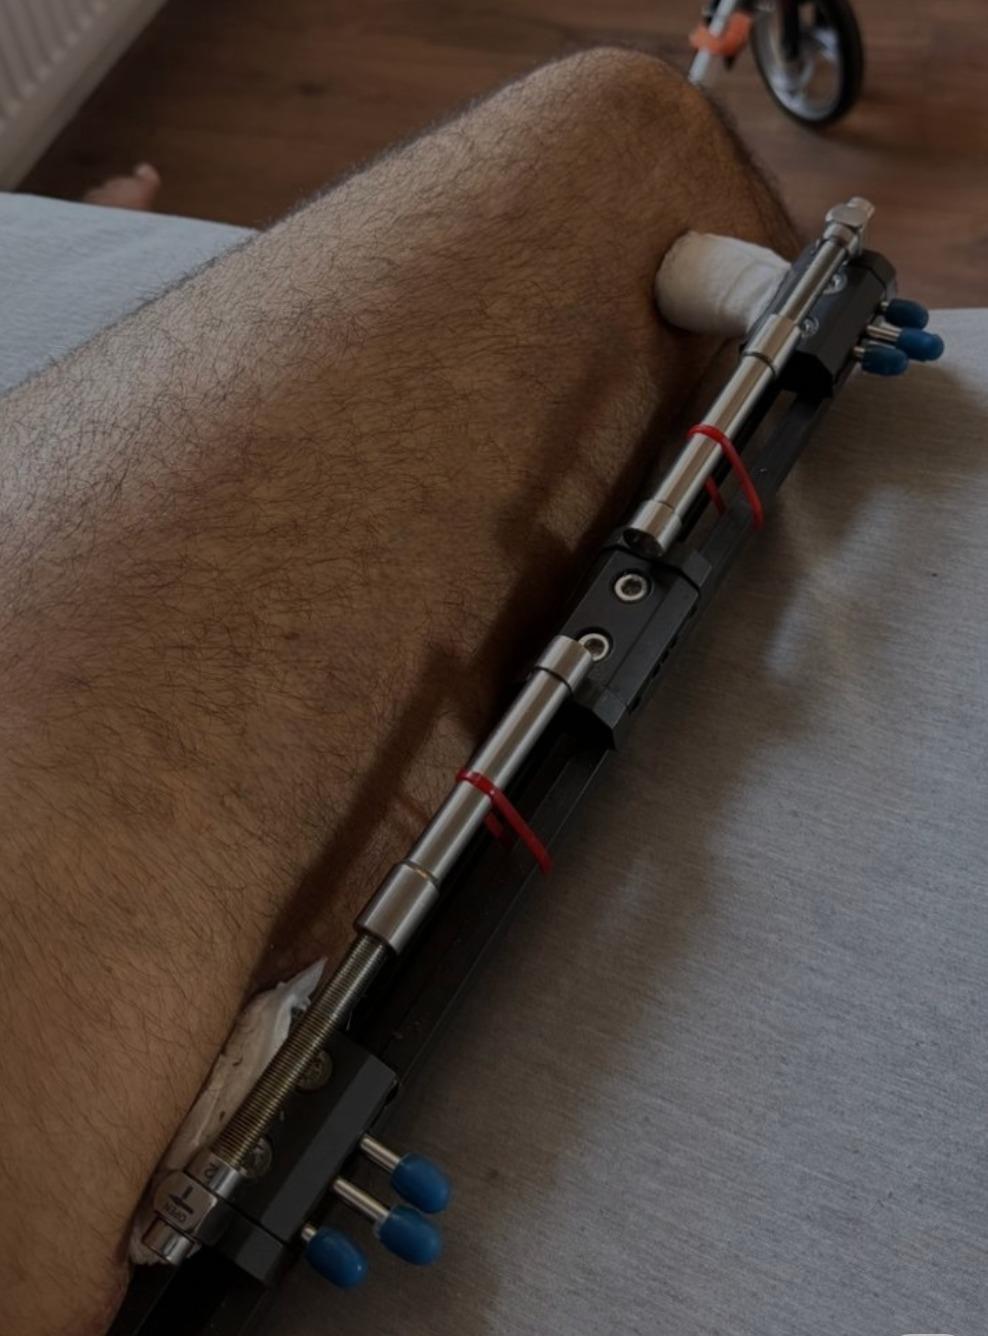

Fitbone Yöntemi

Fitbone® Yöntemi ile Boy Uzatma Tamamen İçten (Internal) Motorize Uzuv Uzatma Teknolojisi